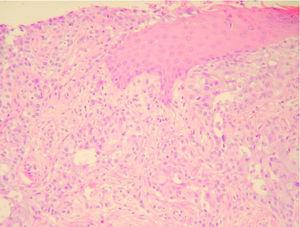

Fig. 3.--En la biopsia cutánea se observa una epidermis ulcerada y una proliferación de células neoplásicas de estirpe epitelial en la dermis. (Hematoxilina-eosina, ×100.)